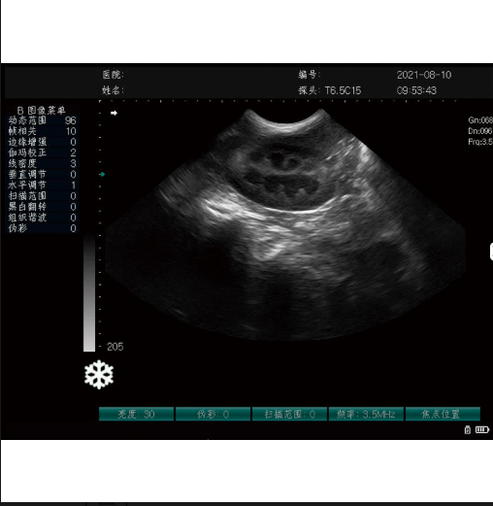

The Gelt G-800 Veterinary Ultrasound Machine delivers high-quality imaging for small and large animals. It offers portability, multi-frequency probes, long battery life, and advanced diagnostic functions—perfect for pregnancy checks, abdominal scans, and general veterinary imaging. Available at the best price in Bangladesh with warranty and fast delivery.

The Gelt G-800 Veterinary Ultrasound Machine is a high-performance diagnostic imaging system designed specifically for veterinary professionals who require quick, accurate, and reliable ultrasound results. Whether you manage a small clinic, a large animal hospital, or a mobile diagnostic service, the G-800 offers the perfect balance of advanced imaging technology, low price, and user-friendly operation. This machine has rapidly become one of the best veterinary ultrasound systems in Bangladesh, trusted by veterinarians for its exceptional image clarity, durable build quality, and outstanding efficiency.

The Gelt G-800 is built for a wide range of animals—pets, livestock, farm animals, and large animals. It delivers exceptional imaging performance for pregnancy detection, reproductive assessment, abdominal scanning, soft tissue evaluation, cardiac monitoring, and other veterinary applications. With its innovative imaging algorithms, high-resolution display, and powerful multi-frequency probe support, this ultrasound machine ensures sharp, detailed, and accurate visuals that help veterinarians make quick clinical decisions and improve patient outcomes.

The machine features multi-angle imaging, deep penetration, auto-optimization, high-contrast resolution, and fast frame processing. These features allow veterinarians to quickly identify abnormalities or confirm pregnancy with minimal effort. The user interface is designed so even first-time users can operate it comfortably.